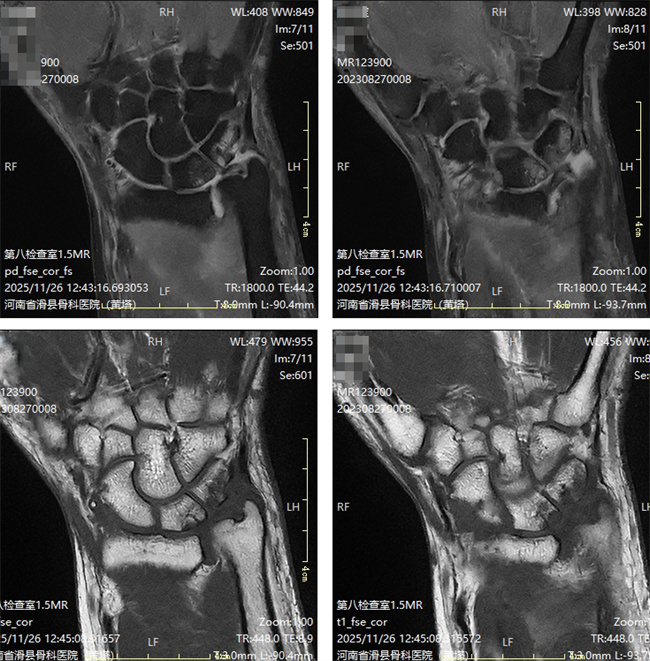

二、患者张某某,男,55岁,患者右肘部疼痛1年余,腕部疼痛肿胀麻木,活动受限。为求进一步治疗,来到我院请专家会诊,通过各位专家会诊查体、查看影像资料并细致认真的分析后,诊断为:痛风性关节炎,意见:住院治疗。